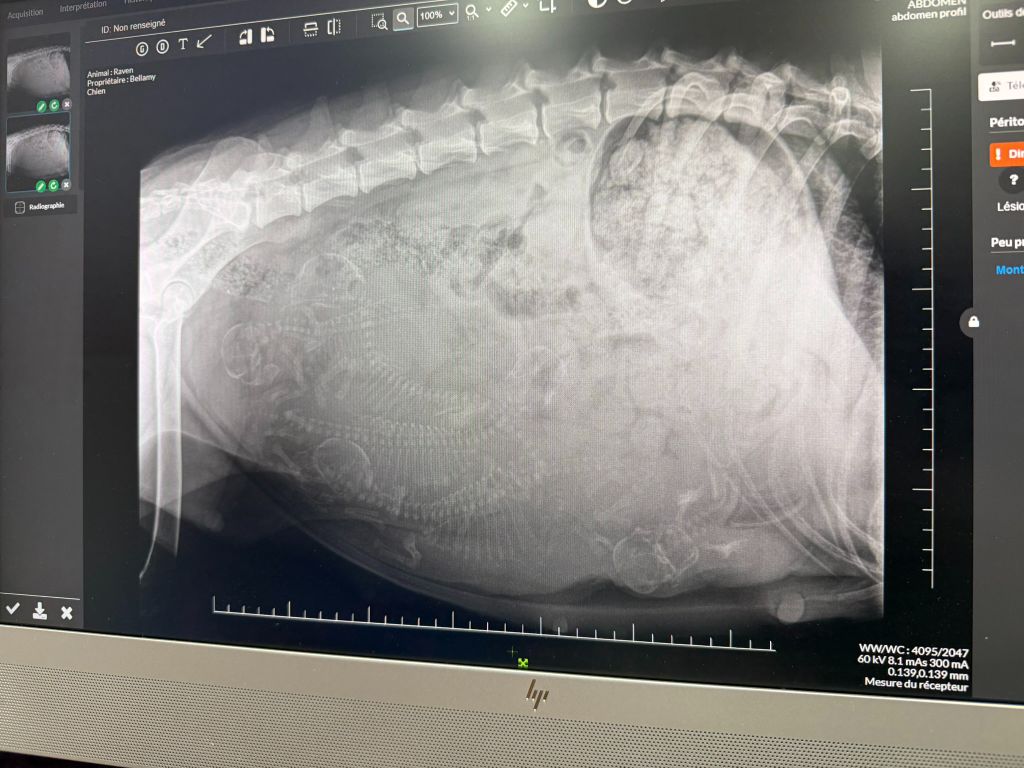

Portée 2025 Raven